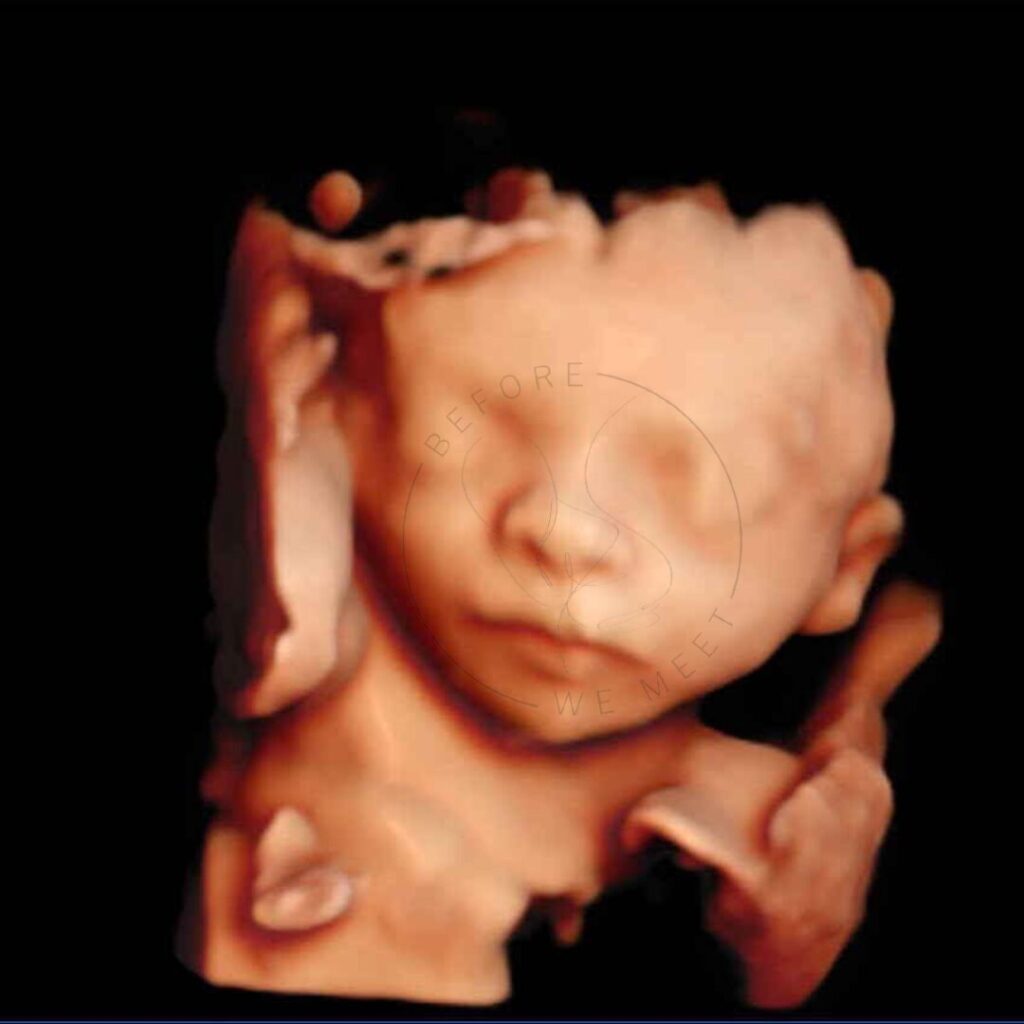

Een 3D/4D echo is éxtra bijzonder doordat we de baby met al zijn of haar details kunnen zien in stilstaande en bewegende beelden. Op wie lijkt zijn/haar neusje? Heeft hij/zij al bolle wangetjes? Of misschien zien we de baby zelfs wel drinken of lachen? Het laat jou (en ons!) verwonderen hoe magisch het nieuwe leven dat in je buik groeit is!

Iedere periode van de zwangerschap vinden wij even bijzonder, juist omdat je per maand zoveel verschil kunt zien. Echter is herkenning van het gezichtje het mooiste tussen de 24e en 30e week van de zwangerschap en afhankelijk van hoe de baby in je buik ligt, of hij/zij zich verstopt achter handjes, voetjes of de placenta en hoeveel vruchtwater er aanwezig is. Mocht het daardoor niet lukken om de baby goed in beeld te krijgen dan mag je nogmaals kosteloos terugkomen voor een echo van 20 minuten.